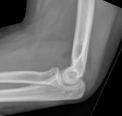

Les résultats peuvent être assez discrets et le seul indice peut être le signe du coussinet adipeux (ombres triangulaires radiotransparentes en avant et en arrière de l'humérus distal sur la radiographie latérale, indiquant une hémarthrose et un déplacement du coussinet adipeux intra-articulaire - souvent associé à une lésion squelettique intra-articulaire).

Image du signe du coussinet adipeux du coude (Hellerhoff (own work), via Wikimedia Commons) :

Signe du coussinet adipeux du coude

© James Heilman, MD, CC BY-SA 4.0, via Wikimedia Commons